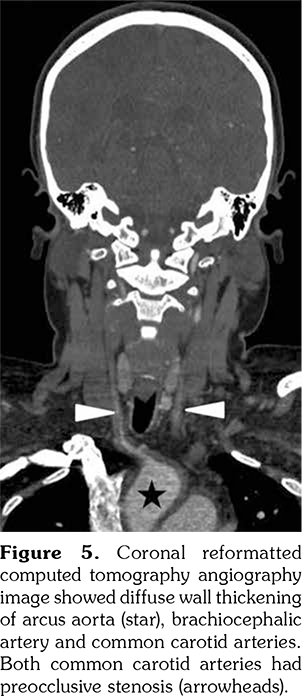

A 14-year-old female patient referred to our clinic with headache and dizziness for two weeks and loss of consciousness for about 10 minutes. On admission, the blood pressure was 90/60 mmHg and all peripheral pulses were palpable. Her body weight was above 97th percentile for her age and body mass index was 33. The fundus examination and other organ systems were essentially normal. Laboratory studies revealed erythrocyte sedimentation rate (ESR) as 108 mm/hour and C-reactive protein (CRP) as 7.5 mg/dL (0-0.8), while other measurements were normal. Urinalysis revealed microscopic hematuria and proteinuria of 31.9 mg/m2/hour in 24-hour urine collection. The cerebrospinal fluid examination showed no abnormalities. Cranial magnetic resonance imaging (MRI) showed multiple millimetric hyperintense deep white matter lesions on T2-weighted imaging (Figure 1). Intracranial and extracranial arteries were normal in magnetic resonance angiography (MRA). Renal biopsy findings were interpreted as FSGS (Figure 2). Patient was considered as cerebral vasculitis and incidental FSGS. Pulse methylprednisolone therapy for three consecutive days was initiated and continued with oral prednisolone. At four years of follow-up, proteinuria decreased to 5-15 mg/m2/hour, and ESR and CRP were normal. Repeated brain MRI and MRA examinations showed no new lesions. Four years later, at the age of 18, on a routine examination, both radial artery pulses were absent and the blood pressure could not be measured. Significant bruit was heard on the left carotid artery. Laboratory studies revealed ESR as 43 mm/hour and CRP as 2.46 mg/dL. Aortic MRA revealed diffuse wall thickening and contrast enhancement in the arcus aorta and its many main branches (Figure 3). Takayasu arteritis diagnosis was established according to the European League Against Rheumatism/ Paediatric Rheumatology International Trials Organisation/Paediatric Rheumatology European Society criteria.[2] Methotrexate was begun, and daily prednisolone was continued. Four months after the diagnosis of TA, left-sided hemiparesis developed. Brain MRI demonstrated a wide cerebral infarct at the right anterior vascular territory (Figure 4). Brain and neck computed tomography angiography showed total occlusion of the right internal carotid artery. Vascular involvement of the right common carotid artery was progressed to preocclusive stenosis. Diameters of the right anterior and middle cerebral arteries were thin and fed by the posterior and anterior communicating arteries (Figure 5). Tocilizumab treatment was started at 8 mg/kg every four weeks. At follow- up with 2.5 years of tocilizumab treatment, the patient's clinical condition improved slightly, and no new symptoms developed. A written informed consent was obtained from the patient.

Several causes of ischemic stroke in patients with TA have been described, including embolism from stenotic or occlusive lesions in the aortic arch and its main branches or cardiac diseases.[6] In addition, intracranial stenosis have been observed as a consequence of vasculitic involvement or a prior embolization into the vessel. In our patient, based on the MRI scan, this cerebral accident seemed to be a vascular occlusion.